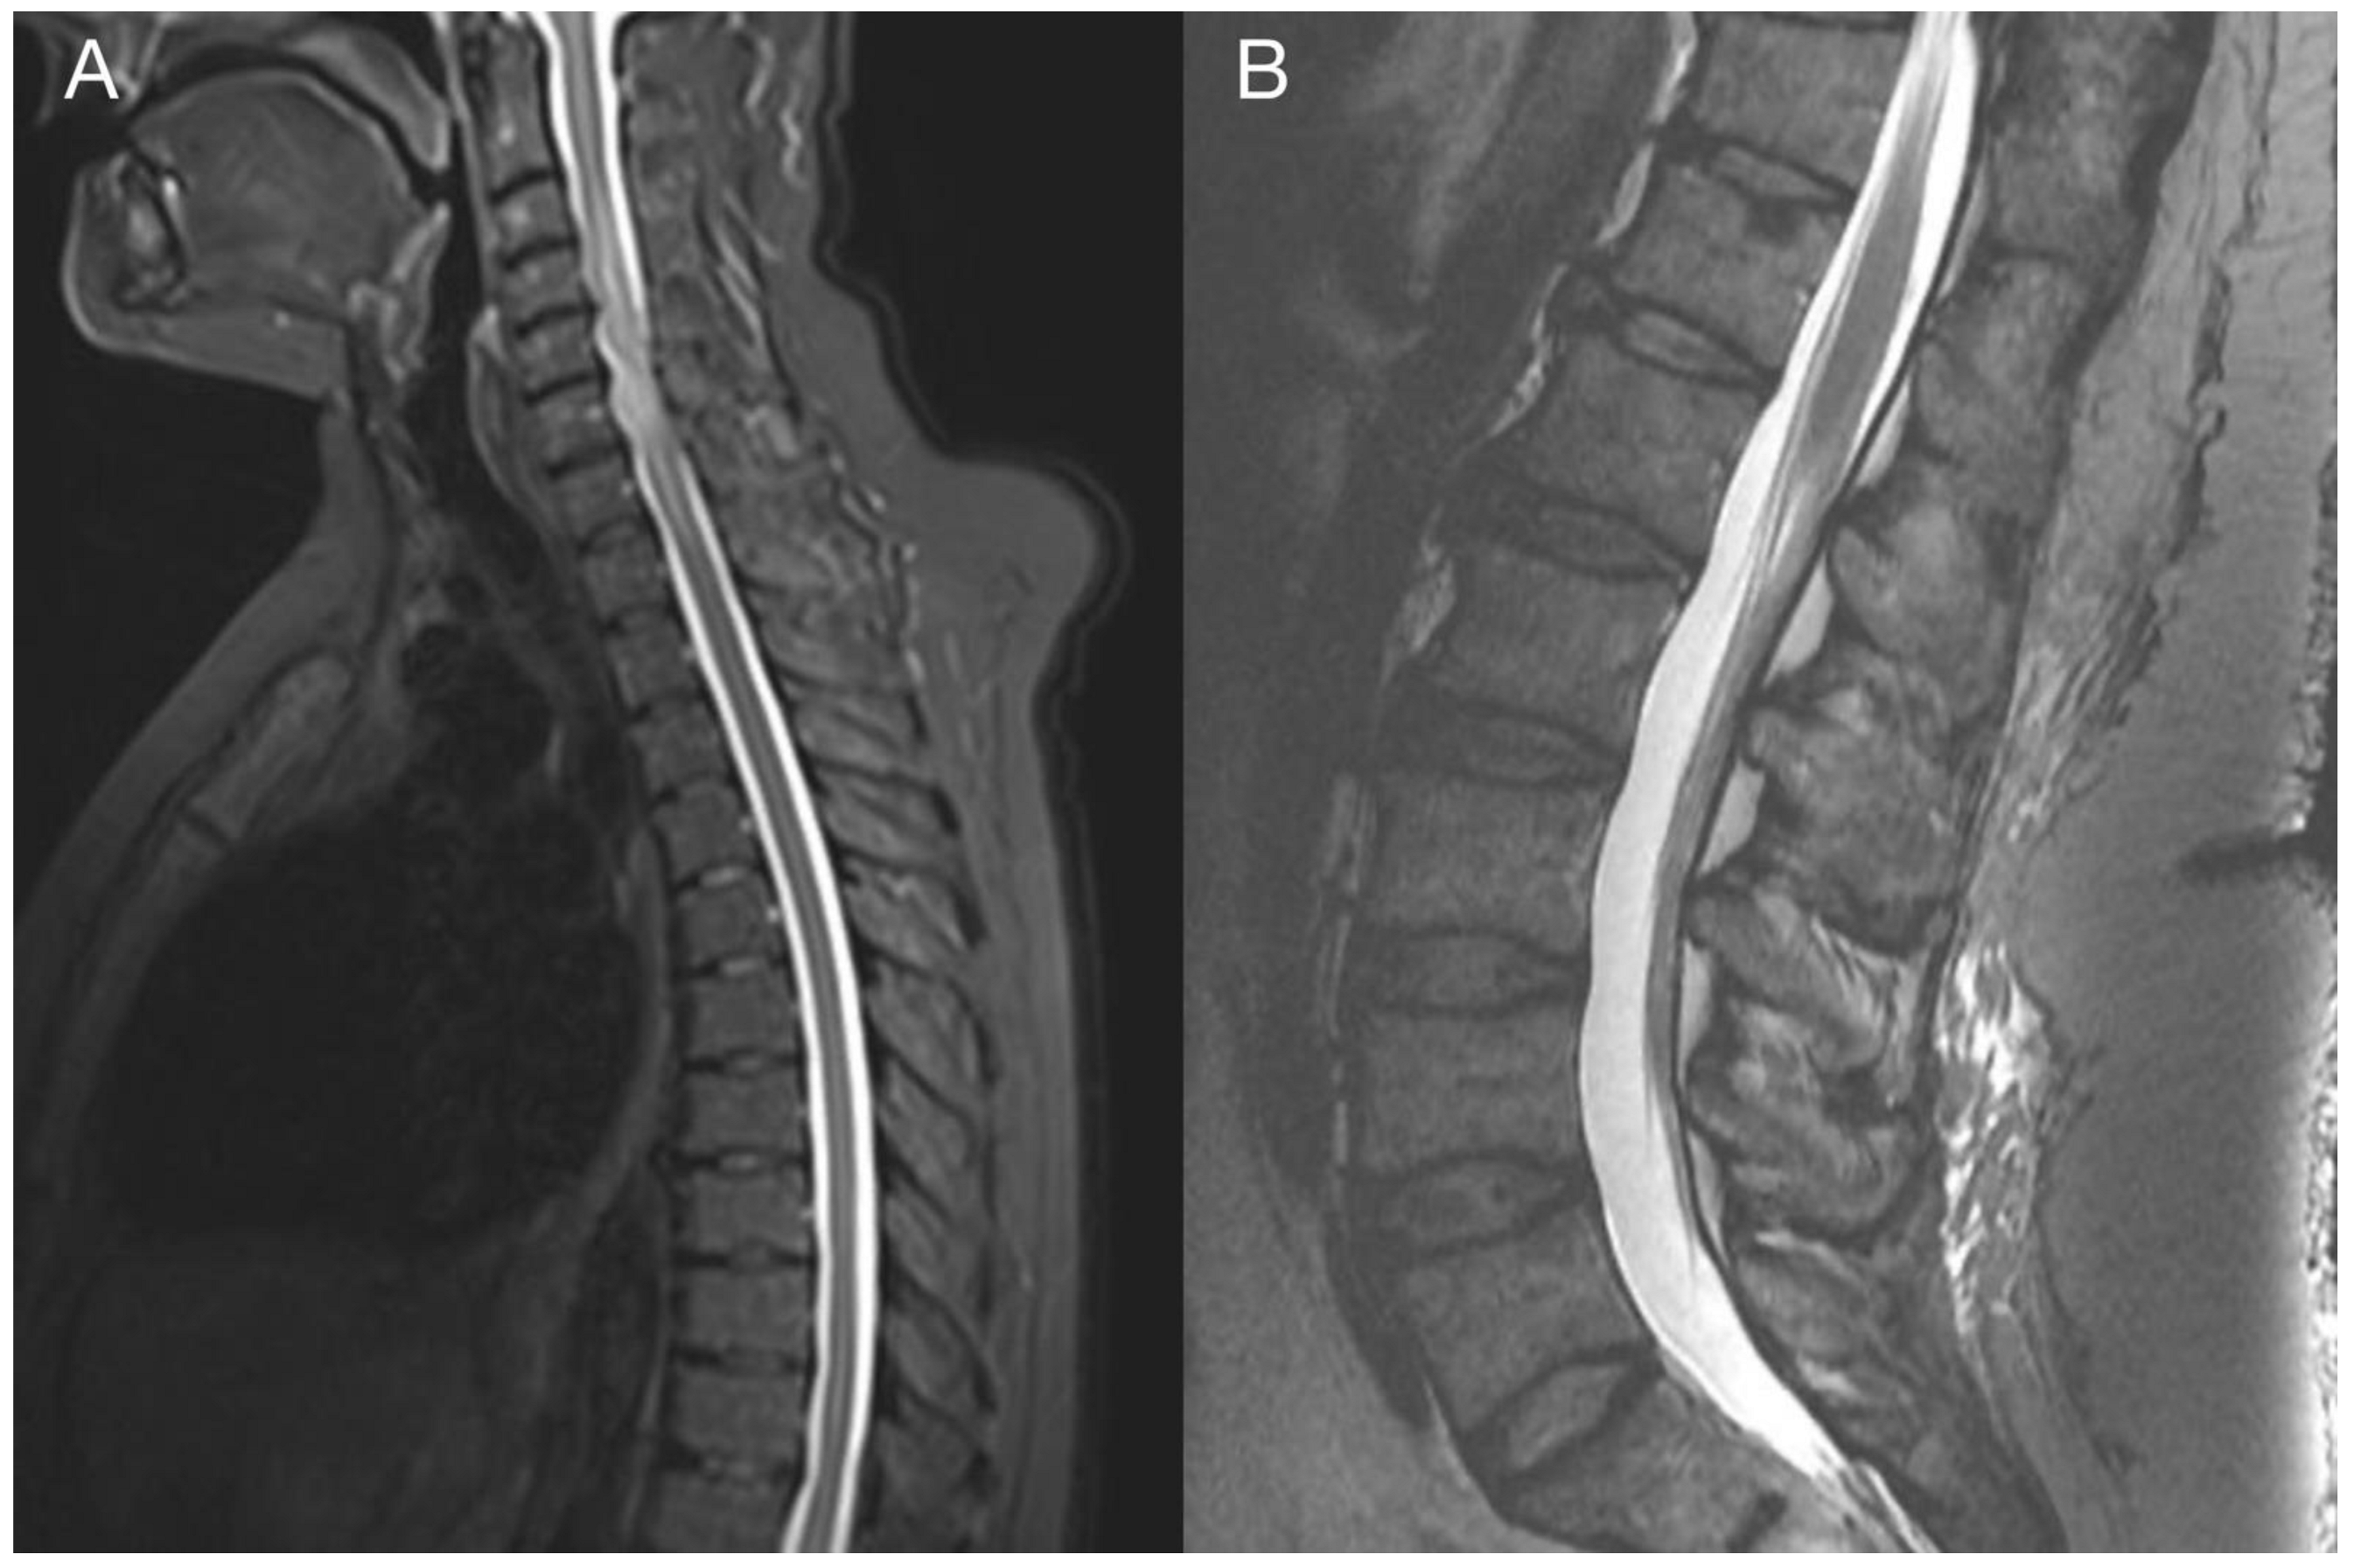

Figure 6.

Imaging of the spinal metastasis. Five-month postoperative cervical spine MRI (postcontrast T1 weighted images) showing intradural expansion (arrow) at the C6 level intimately related to the spinal cord with spinal cord compression (A). Axial section showing intradural expansion (arrow) partially encircling the spinal cord and spreading into the neural foramen (B).

Figure 7.

Imaging of the thoracic and lumbar spine. Preoperative MRI of the thoracic (A) and lumbar spine (B) did not show other pathological changes related to GBM metastasis.